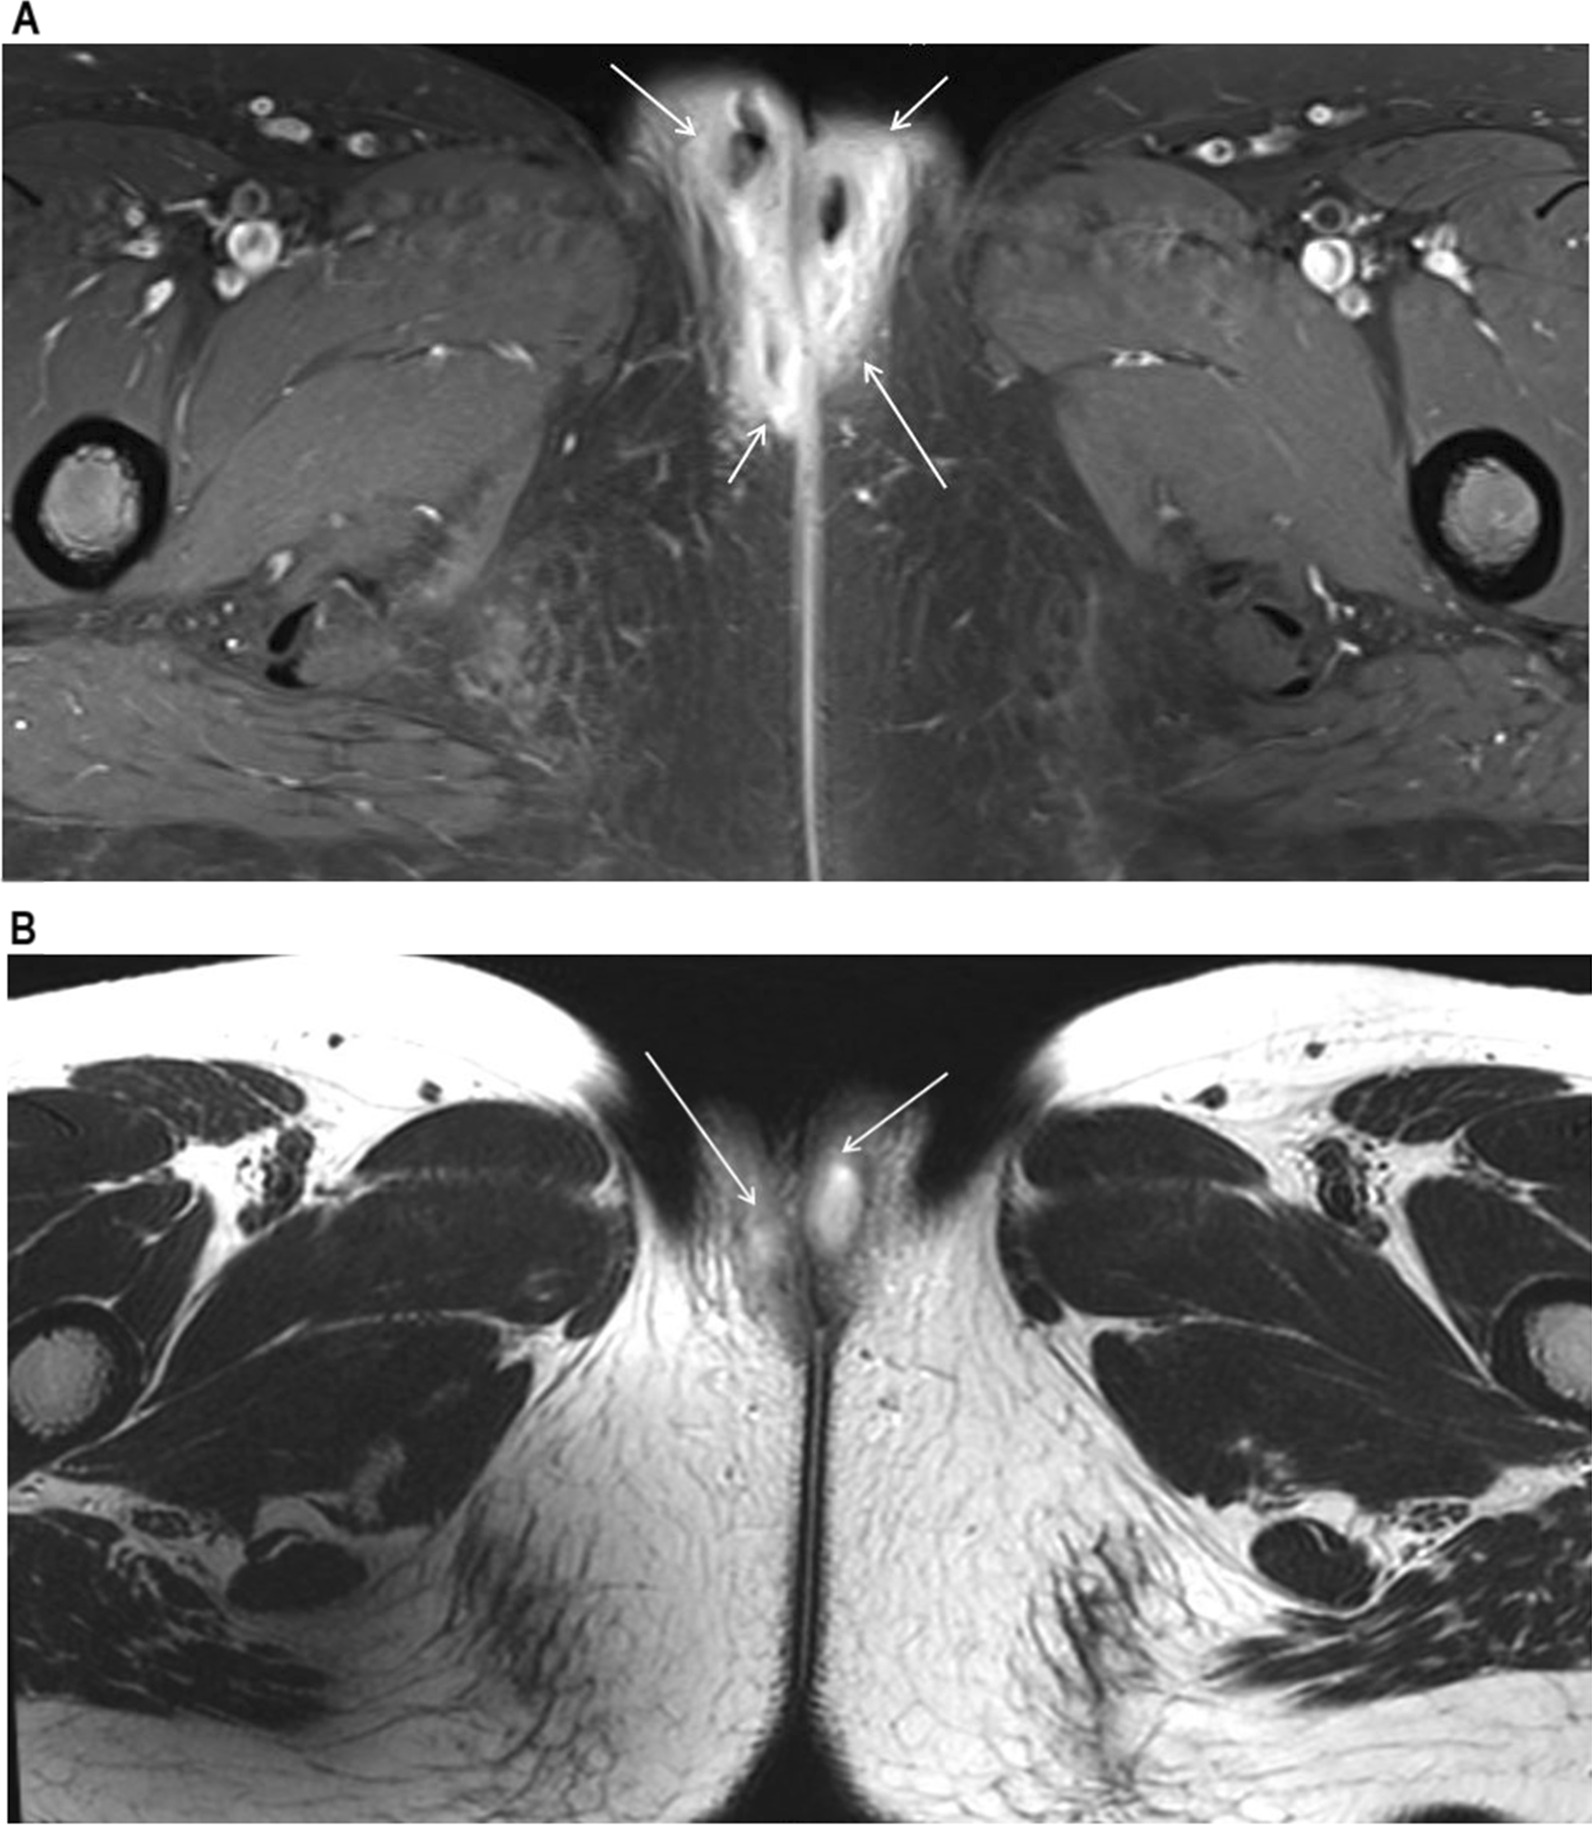

Fig. 2.

MRI image showing vulvar abscess. A Axial view of pelvic MRI prior to I&D at previous hospital with soft tissue infiltration and enhancement in both labia major and perineum (arrow: soft tissue inflammation and swelling with abscess). B Follow-up MRI taken 6 weeks postoperatively at our institution (arrow: abscess)

She was referred to our institution, a tertiary care hospital. At the pediatric and adolescent gynecology clinic, a follow-up MRI was performed because the features of the abscess were not typical of a gynecological abscess. A deep pelvic abscess, at a higher level than Bartholin abscess, was suspected. The MRI results showed diffuse inflammation of the perineum around the posterior vaginal wall with abscess formation along both vestibular glands as well as both labia major and minor. There were also features suggestive of a rectovestibular fistula at the 12–1 ‘o’clock position (Fig. 2B). The patient was then clinically evaluated for Crohn’s disease because of the above MRI findings. Her laboratory tests, including inflammatory markers, were normal.

MRI enterography after oral contrast ingestion showed segmental and uneven wall thickening with ulcerative lesions from the distal to the terminal ileum and distal rectum with increased mucosal enhancement and diffusion restriction (Fig. 4). Diffuse bilateral perineal soft tissue infiltration and increased enhancement with features suggestive of a rectovaginal (11 ‘o’clock) and a vaginoperineal (bilateral anterior) fistula were also observed. The abscess in both vestibular glands and both labia were smaller in size compared to those in the pelvic MRI performed the previous month at the gynecology department. The Pediatric Crohn’s Disease Activity Index (PCDAI) was 12.5, which indicated clinical response (≤ 12.5), but not inactive disease (< 10) [14]. The modified PCDAI score was 2.5, indicating remission (< 7.5) [15].